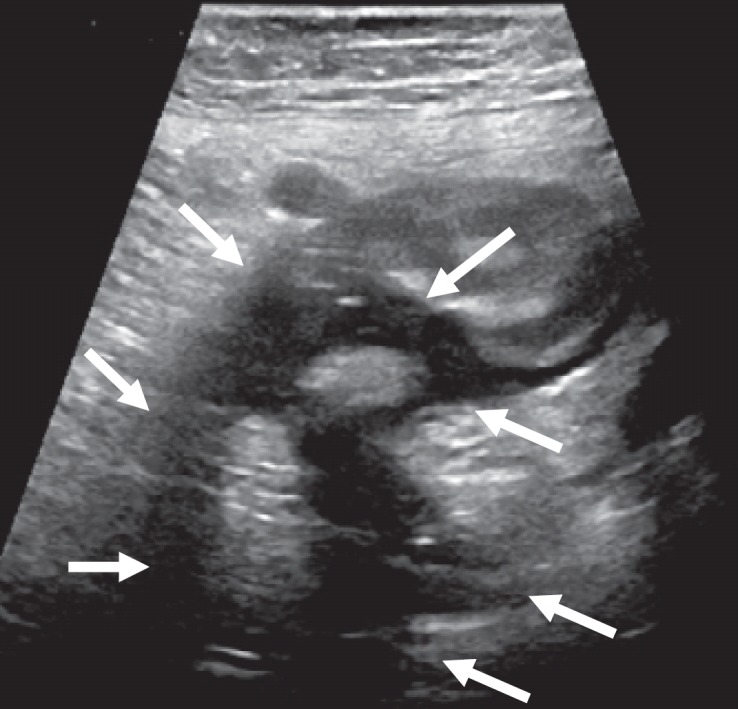

US is applied directly at the point of pain and guarding, which usually reveals the inflamed diverticulum and/or associated complications (fig. 3a, b).

Fig. 3.

Sonographic findings in a patient with diverticulitis. a Well-defined, broad mucosal layer of the outpouched diverticulum surrounded by an echo-rich mesenteric reaction (arrows) representing ‘The diverticulum with different echogenicity in the centre of a pericolonic fatty tissue reaction’ (Hollerweger [46]). The orifice and neck of the diverticulum are indicated by the dotted arrow. b Circle pointing to discrete air bubbles in the mesenteric fat defining a type 2a acute diverticulitis (which is not recognized in fig. 3a representing type 1a). Stars indicate broadened colonic wall diameter and some inflammatory swelling of the mucosa at the orifice of the diverticulum.

The core US finding of diverticulitis (figs. 3, 4) is ‘The diverticulum with different echogenicity in the centre of a pericolonic fatty tissue reaction’ (Hollerweger [46]), i.e. surrounded by an echogenic mesenteric cap, in conjunction with i) hypoechoic and initially asymmetrical wall thickening (>5 mm) with loss of wall layering, reduced wall compliance under pressure, and narrowing of the lumen, and ii) occasionally hypoechoic ‘inflammation lanes’ which are considered inflammatory exsudation (fig. 4b at 10:30 clockwise orientation).

Microperforations, fistulas, and abscesses are characterized by air bubbles in the mesenterium, in a hypoechoic lane, or in an echo-poor fluid retention, while free peritoneal air or air bubbles in the retroperitoneal space indicate free or retroperitoneal perforation.

In experienced hands, sensitivity and specificity of US are 98% [38]. In uncomplicated diverticulitis, direct visualization of the inflamed diverticulum amounts to 96%; however, it is more difficult if complications dominate (77%, specificity 99%) [46].

Deep abscesses, mesenteric air, and retroperitoneal perforation are the most difficult triad for US in this scenario, and the examiner should especially consider this if US produces an ‘unsatisfactory picture’ which is in contrast with an obviously ‘ill’ patient. This then becomes a case for CT; however, detection of diverticula or diverticular inflammation at CT has only insufficient sensitivity (30%) and interobserver agreement (despite an overall 99% sensitivity and specificity) [47,48].